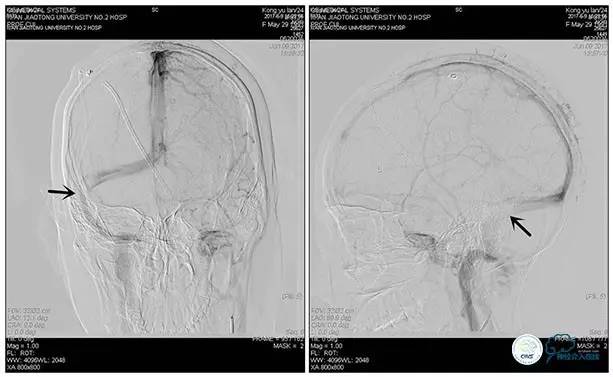

术中右侧ICA造影

右侧ICA斜位及窦内造影

右侧ICA斜位

窦内造影及路图

术中测压:

远端:520mmH2O,

近端:190mmH2O。

治疗方案:

1、8mm×40mm , EverCross球囊扩张;

2、8mm×40mm,Protégé自膨支架成形术。